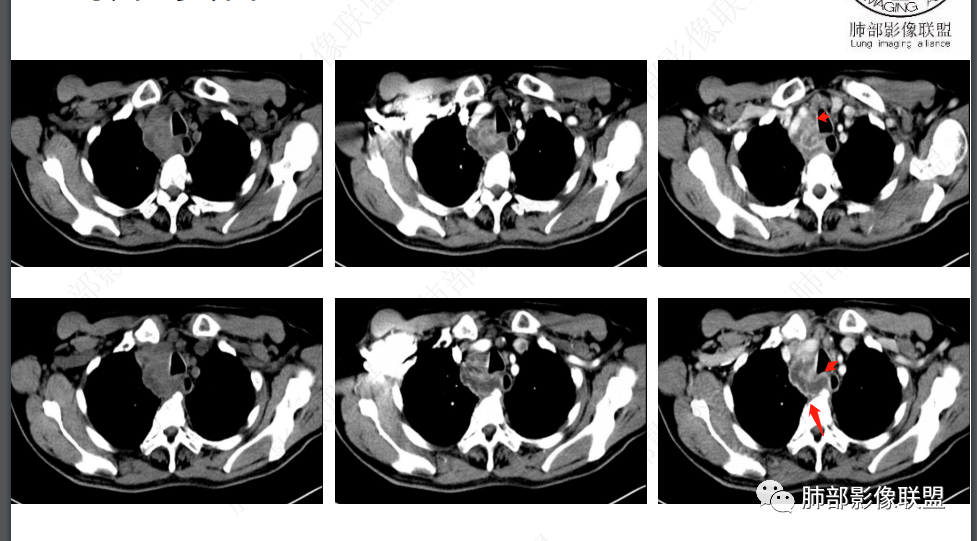

1、 临床特点:老年男性,慢性病程,午后低热为主,既往抗结核治疗有效,停药后复发,MTB抗原ESAT-6和CFP-10阳性,T-SPOT实验(+);查体:右颈部及右腹股沟区多发肿大淋巴结。

2、影像特点:双肺多发结节及条索影,边缘清晰,右肺上叶可见网格影,右侧胸腔少量积液;颈部、纵膈及腹部多发淋巴结肿大,大部淋巴结强化不均,呈环形强化,内部见低密度坏死区,部分淋巴结坏死不明显,尤其是腹部淋巴结密度较均匀。